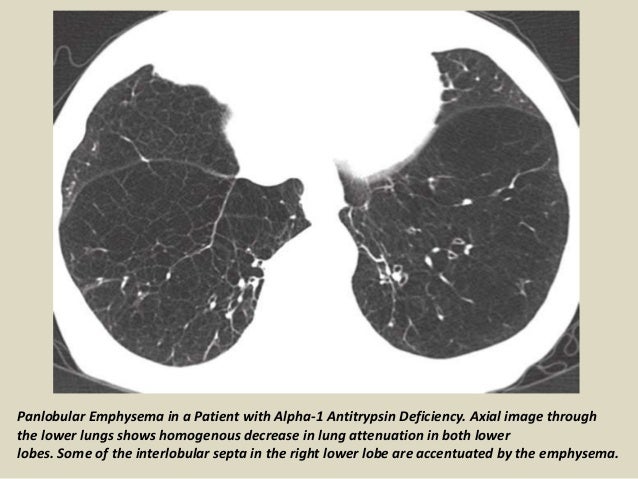

Which emphysema affects the upper lobes of the lungs?

Rarely, emphysema is caused by an inherited deficiency of a protein that protects the elastic structures in the lungs. This condition is called called alpha-1-antitrypsin deficiency.